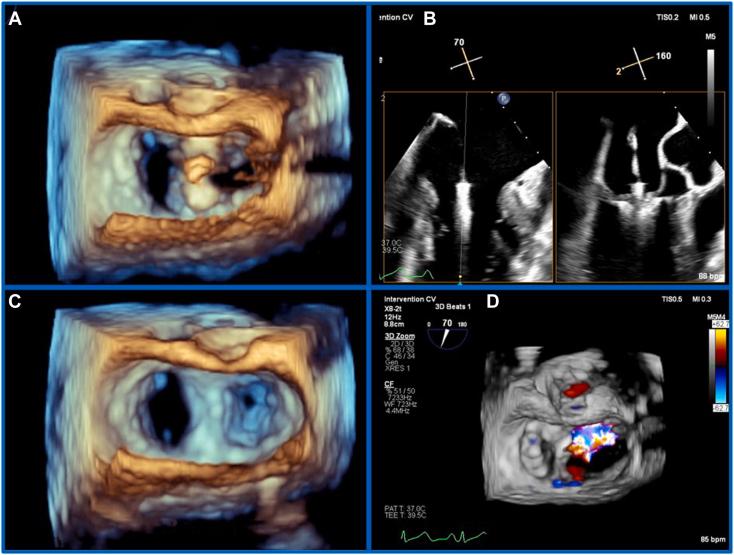

用于具有挑战性的二尖瓣经导管缘对缘修复术中引导的三维实时多平面重建

Three-Dimensional Real-Time Multiplanar Reconstruction for Intraprocedural Guidance of Challenging Mitral Transcatheter Edge-to-Edge Repair.

• 3D MPR allows simultaneous viewing and manipulation of intersecting 2D planes. • Mitral TEER demands intuitive anatomic displays and optimal imaging precision. • 3D RT-MPR simplifies complex multidevice and unfavorable anatomy cases. • Lower resolution in the 3D-derived 2D planar images is a current limitation.

摘要

• 三维多平面重组(3D MPR)允许同时查看和操作相交的二维平面。

• 二尖瓣经导管边缘对边缘修复术(Mitral TEER)需要直观的解剖显示和最佳的成像精度。

• 三维实时多平面重组(3D RT-MPR)简化了复杂的多装置和解剖结构不佳的病例。

• 三维衍生二维平面图像的分辨率较低是目前的一个限制。